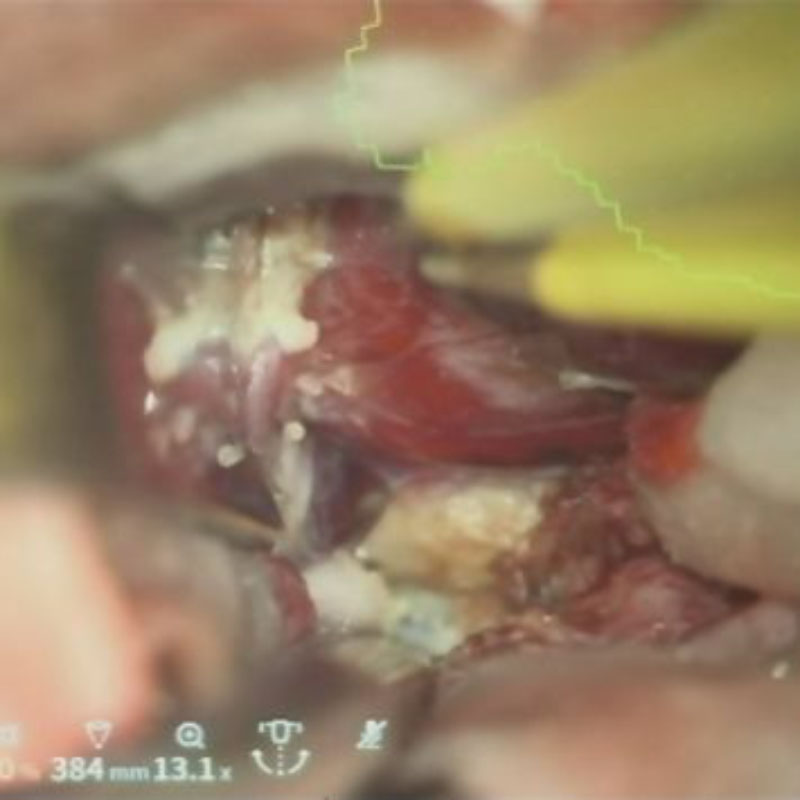

No.’25_88  摘出 中

No.’25_88 摘出 後